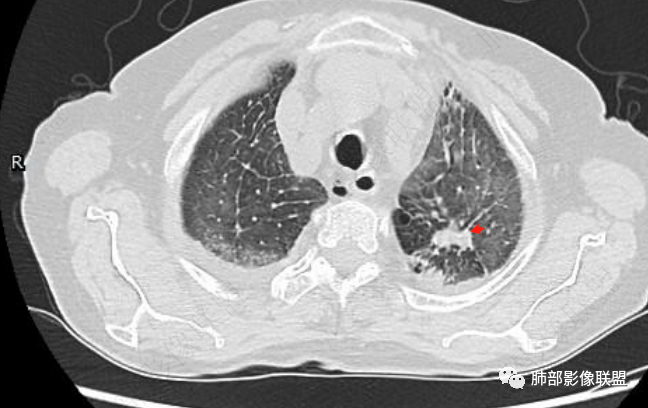

心脏大,胸腔积液,小叶间隔增厚,双肺磨玻璃影,考虑存在肺水肿,另双肺间质性炎性,类风关病史,考虑CTD-ILD,左肺上叶结核可能。

两肺叶后肋膈角区见多发蜂窝状结构破坏表现,双肺叶小叶间隔增厚,左肺上叶后段及舌段和右肺中叶胸膜炎性肉芽肿特点,双侧胸腔少量积液,有类风湿性关节炎治疗史,结缔组织相关性间质性肺病。

①影像表现复杂:较弥漫间质性改变,对称磨玻璃密度为主,小叶间隔增厚,有一定重力分布趋势,未见明显纤维化,气囊及蜂窝位于肺边缘,未见典型“月弓征”。心脏影增大,双侧胸腔积液。

这即可见于间质性肺病,也可见于真菌感染(如PJP)、病毒感染,类风湿,以及肺水肿等等。

一般而言,如存在磨玻璃密度影浑浊,有重力分布趋势,肺表面蜂窝影,胸腔积液等等,并不常见于单纯PJP,除非其他因素叠加。